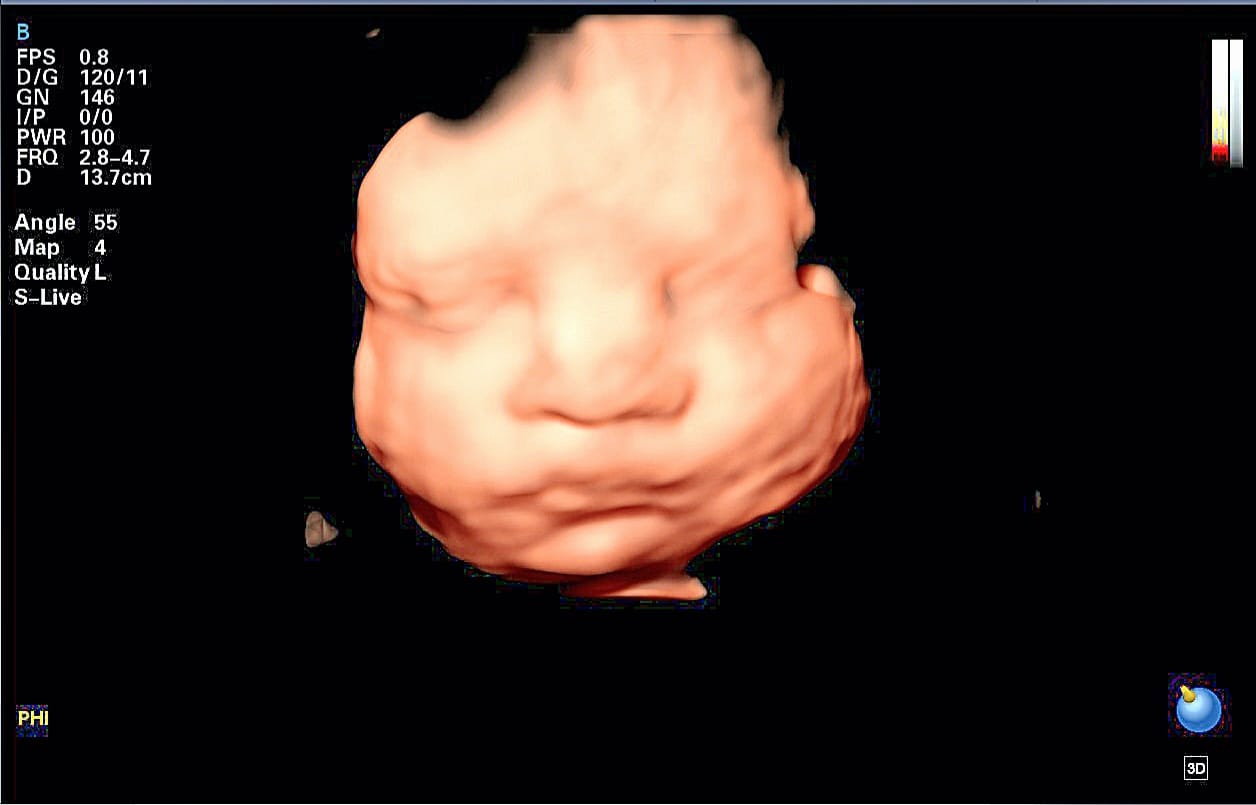

- 1 FOTO DE LA CARITA DE TU BEBE EN MEDIDA DE 10 X 15 CM.

- Te proporcionamos tecnología en alta resolución, con la cual podrás ver una imagen a color en tiempo real de tu bebé ,proporciona una visión temprana y más transparente de la anatomía fetal, va más allá de la superficie para revelar hasta sus huesitos, órganos y otras estructuras internas, aportando una mayor capacidad de diagnóstico.

La exploración se realiza entre las 18 y 24 semanas de gestación. Ideal 20 a 22 Semanas de gestación. Durante la exploración, examinamos cada parte del cuerpo fetal, determinamos la posición de la placenta, evaluamos la cantidad de líquido amniótico y medimos el crecimiento fetal. Se presta especial atención al cerebro, la cara, la columna vertebral, el corazón, el estómago, los intestinos, los riñones y las extremidades. Dentro de los objetivos Principales de la Ecografia Morfologica son: